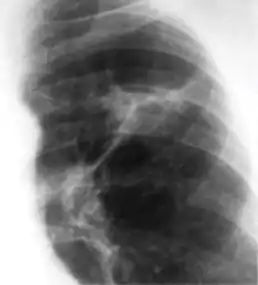

Ghon's complex is a lesion seen in the lung that is caused by tuberculosis.[1][2] The lesions consist of a Ghon focus along with pulmonary lymphadenopathy within a nearby pulmonary lymph node. A Ghons complex retains viable bacteria, making them sources of long-term infection, which may reactivate and trigger secondary tuberculosis later in life.[3]

In countries where cow milk infected with Mycobacterium bovis has been eliminated (due to culling of infected cows and pasteurization), primary tuberculosis is usually caused by Mycobacterium tuberculosis and almost always begins in the lungs. Typically, the inhaled bacilli implant in the distal airspaces of the lower part of the upper lobe or the upper part of the lower lobe, usually close to the pleura. As sensitization develops, a 1- to 1.5-cm area of gray-white inflammation with consolidation emerges, known as the Ghon focus. In most cases, the center of this focus undergoes caseous necrosis. Tubercle bacilli, either free or within phagocytes, drain to the regional nodes, which also often caseate. This combination of parenchymal lung lesion and nodal involvement is referred to as the Ghon complex. During the first few weeks, there is also lymphatic and hematogenous dissemination to other parts of the body.

The Ghon complex undergoes progressive fibrosis, often followed by radiologically detectable calcification (Ranke complex), and despite seeding of other organs, no lesions develop. Although they are often confused, Ranke complex and Ghon complex are not synonymous. The Ranke complex is an evolution of the Ghon complex (resulting from further healing and calcification of the lesion).[4][5]